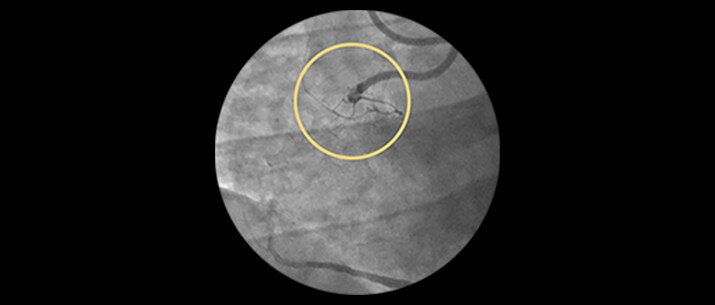

Incidence increases with age, yet older patients are less likely to have PCI attempted.1 Furthermore, 18% of PCIs have a CTO, but less than 5% are being treated.2